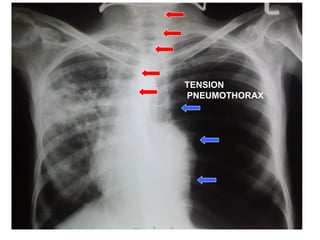

Signs of tension pneumothorax Pleuritic chest pain Respiratory distress  ( dyspnea, tachypnea, ability to speak only in short sentences or single words, agitation, sweating ) •  Falling arterial oxygen  saturation •  Ipsilateral  hyperexpansion,  hypomobility,  hyperresonance with  decreased BS  •  Tachycardia •  Hypotension  •  Tracheal deviation  •  Elevated jugular  venous pressure

Signs of tensionpneumothorax Pleuritic chest pain Respiratory distress ( dyspnea, tachypnea, ability to speak only in short sentences or single words, agitation, sweating ) • Falling arterial oxygen saturation • Ipsilateral hyperexpansion, hypomobility, hyperresonance with decreased BS • Tachycardia • Hypotension • Tracheal deviation • Elevated jugular venous pressure